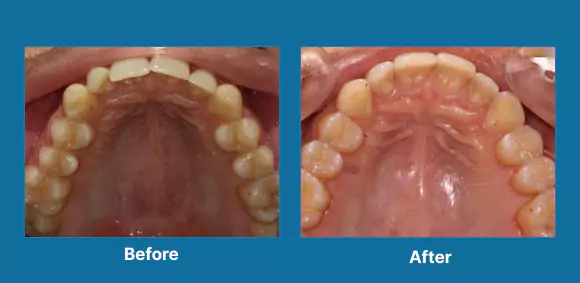

Implants

Full Mouth Rehabilitation